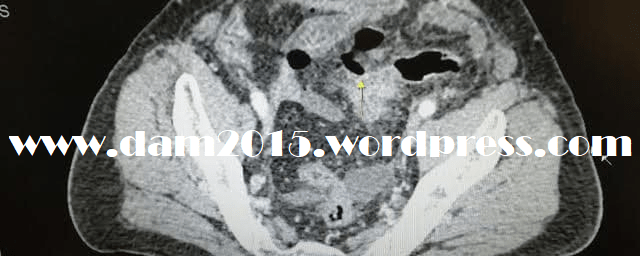

Eseguita TC che mostrava notevole quota di aria libera endoaddominale, maggiormente localizzata in ipogastrio-scavo pelvico, dove si osservava discontinuità della parete del sigma, ed i sede sottodiaframmatica destra. Bolle aeree con associata falda fluida si osservavano anche in sede pericecale.

Marcata distensione con livelli idroaerei delle anse del piccolo intestino, con segni di pneumatosi intestinale a livello del digiuno. Si rilevavano, inoltre, diffusi segni di contenuto aereo lungo le diramazioni venose della vena mesenterica superiore e del ramo di sinistra della vena porta e delle sue diramazioni intraepatiche.